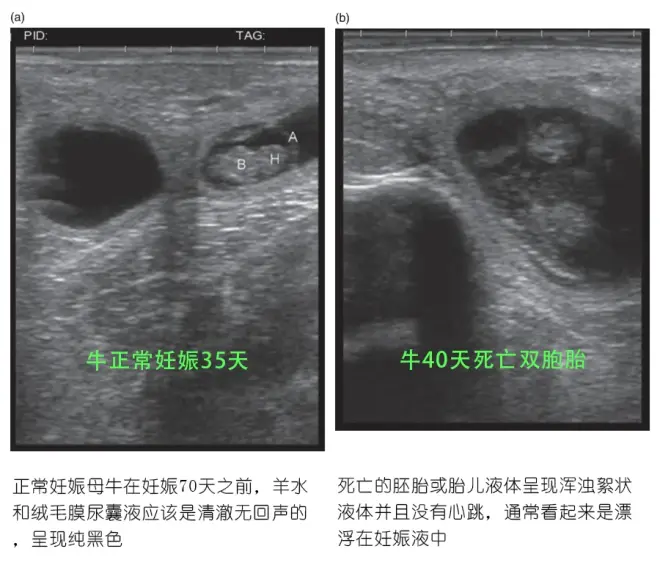

通过使用超声波可以确定胎儿死亡的几个指标,包括:

缺乏胎儿心跳/胎儿活动;

羊水或绒毛尿囊液中存在絮状物质;

绒毛尿囊素与子宫壁的分离。早期发现胚胎/胎儿死亡将减少未怀孕奶牛重新繁殖的时间,从而提高盈利能力。